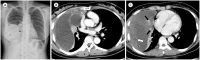

The mediastinum is the most prevalent site of extragonadal teratomas. Patients with mediastinal mature teratomas are usually young adults, and the condition does not show significant sexual differences. Mediastinal teratomas are mostly located in the anterior mediastinum. Patients are usually asymptomatic, although they can have several complications when the teratomas become large or rupture. Most mediastinal teratomas can be diagnosed using CT. Diagnosing ruptured or malignant teratomas is challenging because of their atypical clinical and radiological presentations. In this article, we describe various manifestations of mediastinal teratomas, with an emphasis on radiologic features.